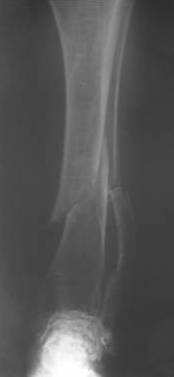

Уважаемые коллеги! Здравствуйте! Прошу у Вас совета вот по какому случаю.В нашу клинику поступила женщина 71 год. Травма в результате ДТП. (Пациентка передвигалась на инвалидной каляске и была сбита автомобилем). Диагноз: Множественная травма. Перелом нижней трети правого бедра. Перелом средней трети правой б/берцовой, малоберцовой кости, нижней трети левой большоберцовой, м/берцовой кости.Травматический шок. Со стороны внутренних органов и систем без патологии. Больная госпитализирована в реанимационное отделение, где было наложено двойное скелетное вытяжение за правую н/конечность. Левая н/конечность иммобилизована гипсовой лонгетой. Из анамнеза: больная является инвалидом 1 группы по опорно-двигательному аппарату. В детстве перенесла рахит. Осложнением которого "О" образная деформация нижних конечностей. Ограничено отведение нижних конечностей, деформирующий артроз тазобедренных и коленных суставов. В 1990 году перелом правого бедра остеосинтез пластиной. После операции больная передвигалась только на костылях или в инвалидной коляске.

Прошу прощения за качество снимков. Р-графия производилась в реанимационном отделении передвижным аппаратом.

Контрольные рентгенограммы прилагаю.